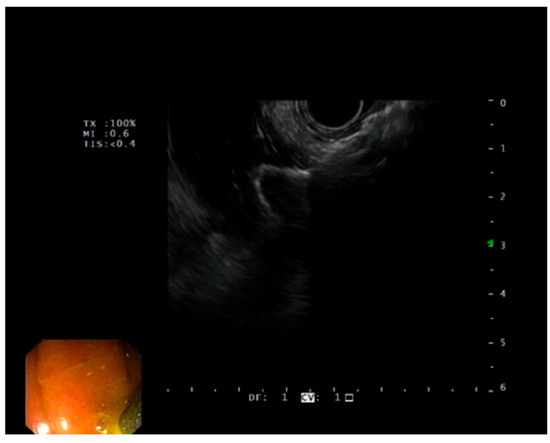

2.2. Study Device

2.3. Procedure

- Mangiavillano, B.; Moon, J.H.; Crinò, S.F.; Larghi, A.; Pham, K.D.-C.; Teoh, A.Y.B.; Paduano, D.; Lee, Y.N.; Yoo, H.W.; Shin, I.S.; et al. Safety and efficacy of a novel electrocautery-enhanced lumen-apposing metal stent in interventional EUS procedures (with video). Gastrointest. Endosc. 2022, 95, 115–122. [Google Scholar] [CrossRef]

- Mangiavillano, B.; Auriemma, F.; Bianchetti, M.; Repici, A. A cholecystoduodenostomy with a new type of lumen-apposing metal stent. Dig. Liver Dis. 2021, 53, 1203. [Google Scholar] [CrossRef]